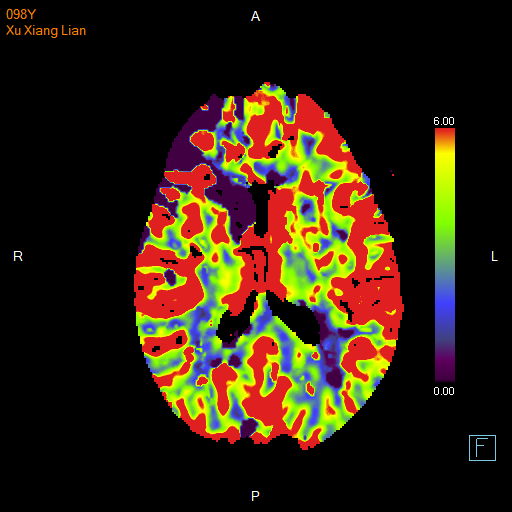

进一步的血管检查(CTA+CTP)发现了更严重的问题:王奶奶的左侧颈内动脉完全闭塞——这是脑梗中最凶险的类型之一,意味着大脑主要供血通道被切断,随时可能危及生命

颅脑 CTP

面对这一严峻挑战,

神经内科介入团队郭钊云医师快速评估后认为:

虽然患者高龄,但发病前身体状况相对稳定,符合急诊动脉取栓术的手术指征,没有手术禁忌症。这是一种通过微创手术直接取出堵塞血管中血栓的先进技术。

与家属充分沟通后,医疗团队决定迎难而上,为王奶奶实施了“取栓支架保护下脑动脉取栓术”,在一个小时内成功将堵塞在左侧颈内动脉及大脑中动脉的大量血栓取出,瞬间恢复了大脑供血。